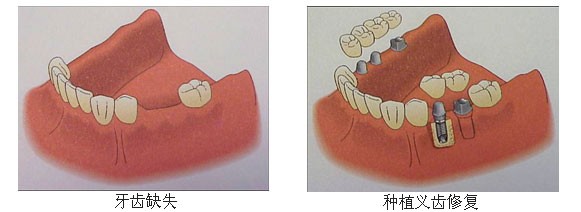

针对牙齿缺失,目前有三种方法可进行修复:活动义齿、烤瓷牙、种植牙。

种植牙:种植牙是目前较理想的缺牙修复方法,无论功能上、美观上、感觉上都是真牙无异。种植牙的“牙根”同样“长”在牙槽骨内,承受与真牙一样的压力、牵拉力与咀嚼力;牙根牢固,牙冠密贴牙龈,无缝对接,因此感觉舒适,无异物感。